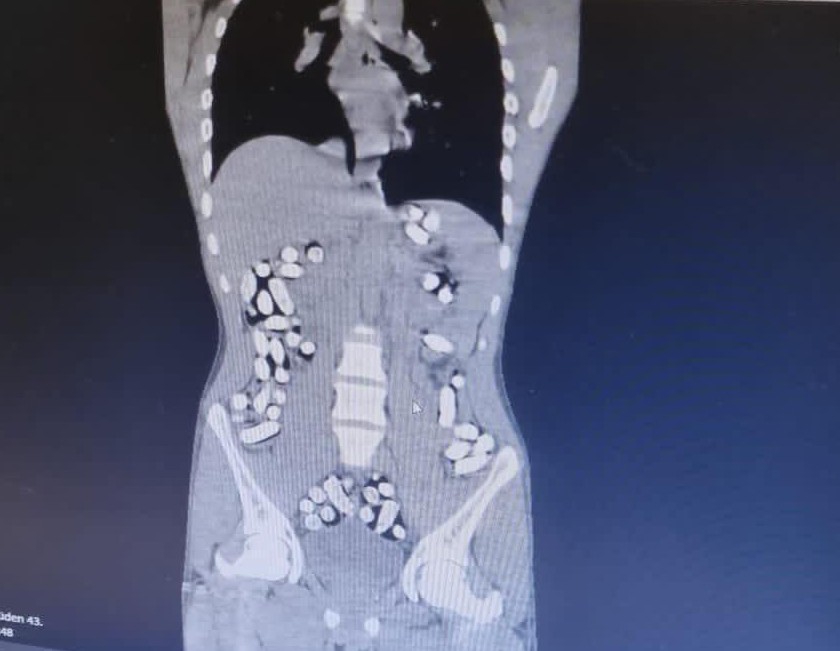

Erzurum Emniyet Müdürlüğü Narkotik Suçlarla Mücadele Şube Müdürlüğü ekipleri, batı illerine uyuşturucu madde nakli yapan şahıs ve araçlara yönelik Erzurum-Erzincan karayolu üzerinde yaptıkları denetimlerde İran’dan ülkeye giriş yapan bir yolcu otobüsünü durdurdu. Kontroller esnasında otobüsteki Mehdı B., Mılad F. ve Sıraus G. isimli şahısların hareketlerinden şüphelenen ekipler, şahısları iç beden muayenesi için hastaneye götürdü. Yapılan muayene ve röntgen çekimi sonrasında şahısların uyuşturucu maddeleri kapsül haline getirerek yuttukları tespit edildi. Doğal yollarla şahısların midelerinden çıkarılan 210 kapsül halinde 3 kilo 192,18 gram afyon sakızı ve 62 kapsül 709,83 gram eroin ele geçirildi.

Bir başka olayda, yine Erzurum-Erzincan karayolu üzerinde İran’dan ülkeye giriş yapan bir araç durduruldu. Araçta bulunan Masoud T. ve Soleman O. isimli şahısların şüpheli hareketler sergilemesi ve üzerlerinde tokluk hissi veren ve mide-bağırsak temizleyici ilaçlar bulunması sebebiyle yutmak suretiyle uyuşturucu madde nakli yaptıklarından şüphelenilerek, muayene için hastaneye götürüldü. Şahısların uyuşturucu maddeleri kapsül haline getirerek yuttukları tespit edildi. 411 kapsül halindeki 2 kilo 953 gram afyon sakızı ele geçirildi.